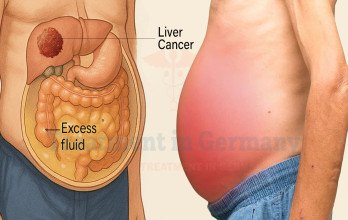

Ascites in liver cancer is a sign of disease progression that requires expert management. Learn why international patients trust German healthcare centers for advanced diagnosis and treatment in Germany.

Details →

Learn how ascites develops in liver cancer and other abdominal cancers, and why German healthcare centers are trusted by international patients in Germany.

Details →

Ascites in hepatocellular carcinoma signals liver dysfunction or tumor spread. Learn how it is diagnosed, monitored, and managed in cancer care settings using imaging and fluid analysis.